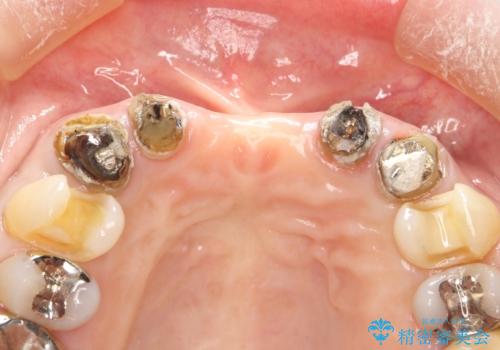

- 仮歯の製作、古い土台(メタルコア)の除去まで行い、根管治療は専門医に依頼

→根管治療終了後、ファイバーコアを築造し、新しいセラミックブリッジを製作した。

一見きれいにはいっているセラミックも、はずして中の状態をみるとひどいことが多い。これは、中の土台の状態や処理のクオリティは、短期的には問題を起こしづらく、患者さんには見えない部分だからです。